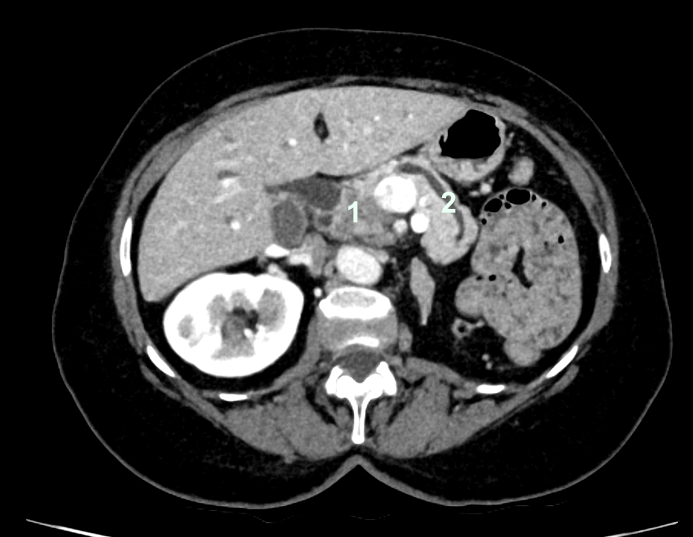

Wenn erstmals die Verdachtsdiagnose eines Bauchspeicheldrüsentumors gestellt wurde, muss die weitere Abklärung und Planung der Therapie sehr sorgfältig erfolgen. Neben der Anamnese und klinischen Untersuchung sind bildgebende Verfahren äusserst wichtig. Dazu gehören die Computertomographie, die Magnetresonanztomographie und die endoskopische Ultraschalluntersuchung. Diese erlaubt auch auf elegantem Weg, Gewebe zur genaueren Differenzierung zu sammeln.